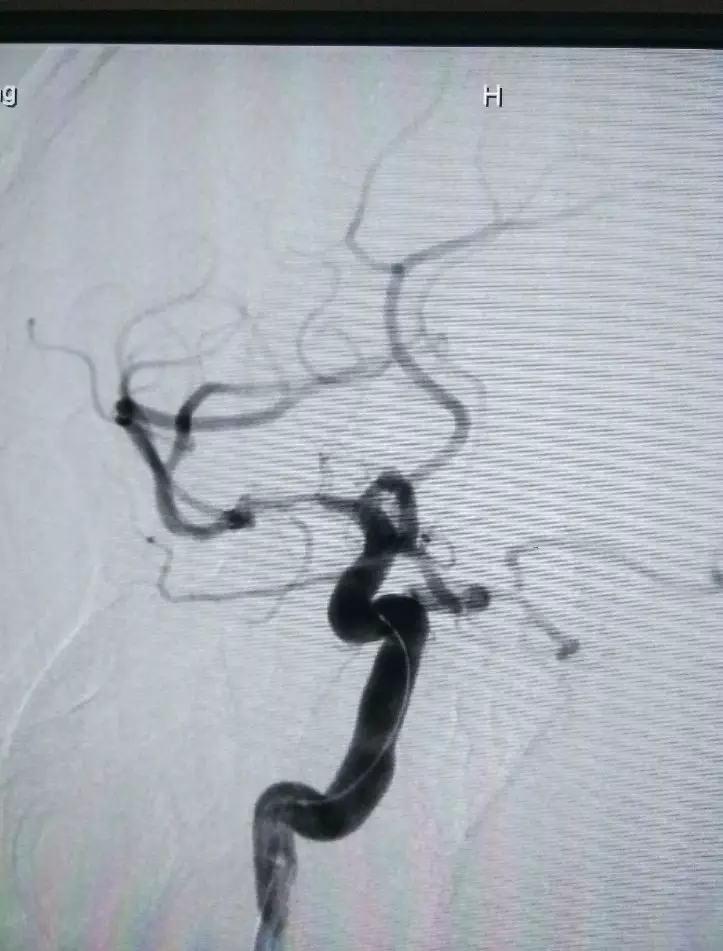

治疗中造影(点击可查看大图)

取栓后造影,发现为原位狭窄,调整为球囊扩张

球囊快速顺畅通过较迂曲的虹吸弯到达病变部位

(Neuro Rx 2.0*10)

球囊扩张4atm(Neuro Rx 2.0*10)

扩张后残余狭窄,且观察10min后再次闭塞

支架释放,扩张效果不佳(Enterprise 4.5x14)

同球囊导管再次支架内扩张6atm(Neuro Rx 2.0*10)

支架后扩张结果